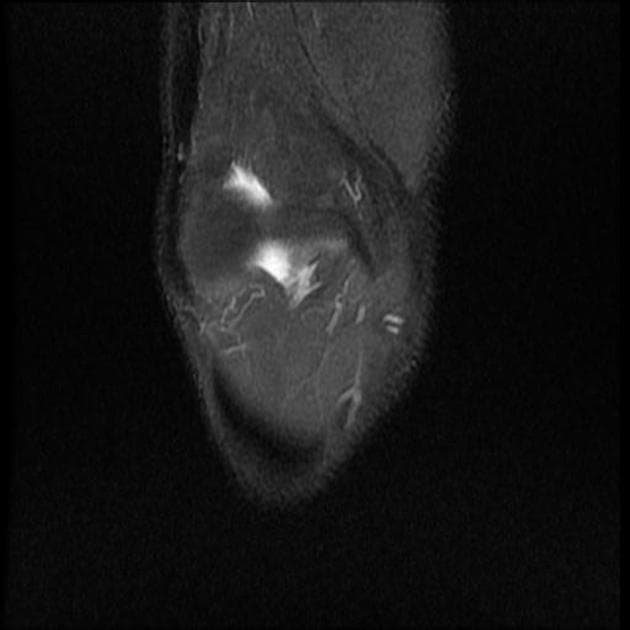

Sagittal PD fat sat

MRI•Sagittal PD fat sat•1 / 31

Ca bệnhChấn thương dạng kẹp – rách dây chằng bên chày và rách sụn chêm trong

Chấn thương dạng kẹp – rách dây chằng bên chày và rách sụn chêm trong

- Phù tủy xương do chấn thương tại lồi cầu ngoài xương đùi và lồi cầu ngoài xương chày.

- Rách một phần dây chằng bên chày (medial collateral ligament – MCL).

- Rách theo chiều ngang sụn chêm trong (medial meniscus tear).

- Tràn dịch khớp (joint effusion).

Một trường hợp chấn thương dạng kẹp (clip injury) ở cầu thủ bóng đá bị tác động lực từ phía ngoài khớp gối, gây tổn thương dây chằng bên chày và sụn chêm trong.

Chấn thương dạng kẹp – rách dây chằng bên chày và rách sụn chêm trong (clip injury - MCL and medial meniscus tear)

Chấn thương dạng kẹp là chấn thương do lực tác động từ phía ngoài khớp gối, thường gặp trong các môn thể thao đối kháng như bóng đá hoặc bóng bầu dục, gây lực dạng lên khớp gối. Cơ chế này thường dẫn đến tổn thương vùng trong khớp gối, đặc biệt là dây chằng bên chày (MCL) và sụn chêm trong. Trong trường hợp này, cộng hưởng từ (MRI) cho thấy rách một phần dây chằng bên chày và rách theo chiều ngang sụn chêm trong, kèm theo phù tủy xương tại lồi cầu ngoài xương đùi và lồi cầu ngoài xương chày do lực ép trực tiếp. Tràn dịch khớp cũng là dấu hiệu hỗ trợ chấn thương cấp tính. Trong khi tổn thương MCL có thể hồi phục bằng điều trị bảo tồn, các tổn thương sụn chêm có thể cần nội soi khớp để đánh giá, đặc biệt khi có triệu chứng cơ học. Chẩn đoán chính xác rất quan trọng để định hướng điều trị phù hợp và ngăn ngừa các biến chứng lâu dài như mất vững khớp hoặc thoái hóa khớp.